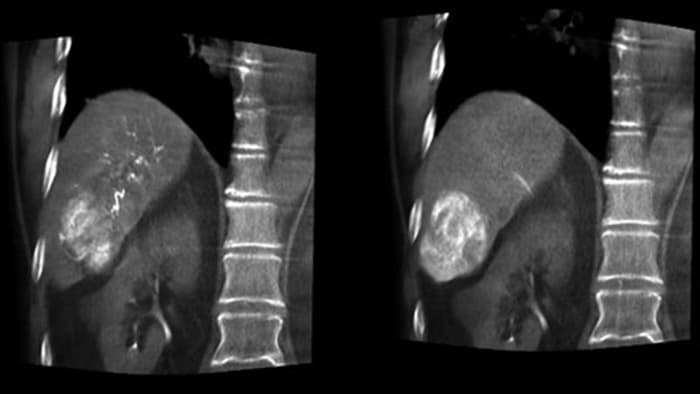

THC Dual permite la adquisición de imágenes en 3D de una fase arterial para visualizar estructuras vasculares y una posarterial (fase retardada) para ver la acumulación del medio de contraste, en un solo paso automático.5

Dual View permite la visualización simultánea de dos conjuntos de datos de la THC. Tanto la fase arterial como la retrasada se pueden mostrar una al lado de la otra o en una sola vista de superposición fusionada.

Una adquisición 3D posterior a la embolización le permite ver el depósito dirigido del material embólico, como Liopidol o perlas radiopacas, en el tumor.5.

Dual View permite ver de forma simultánea la imagen 3D de la fase arterial antes de la embolización y la imagen después de la embolización para evaluar el fin del tratamiento.